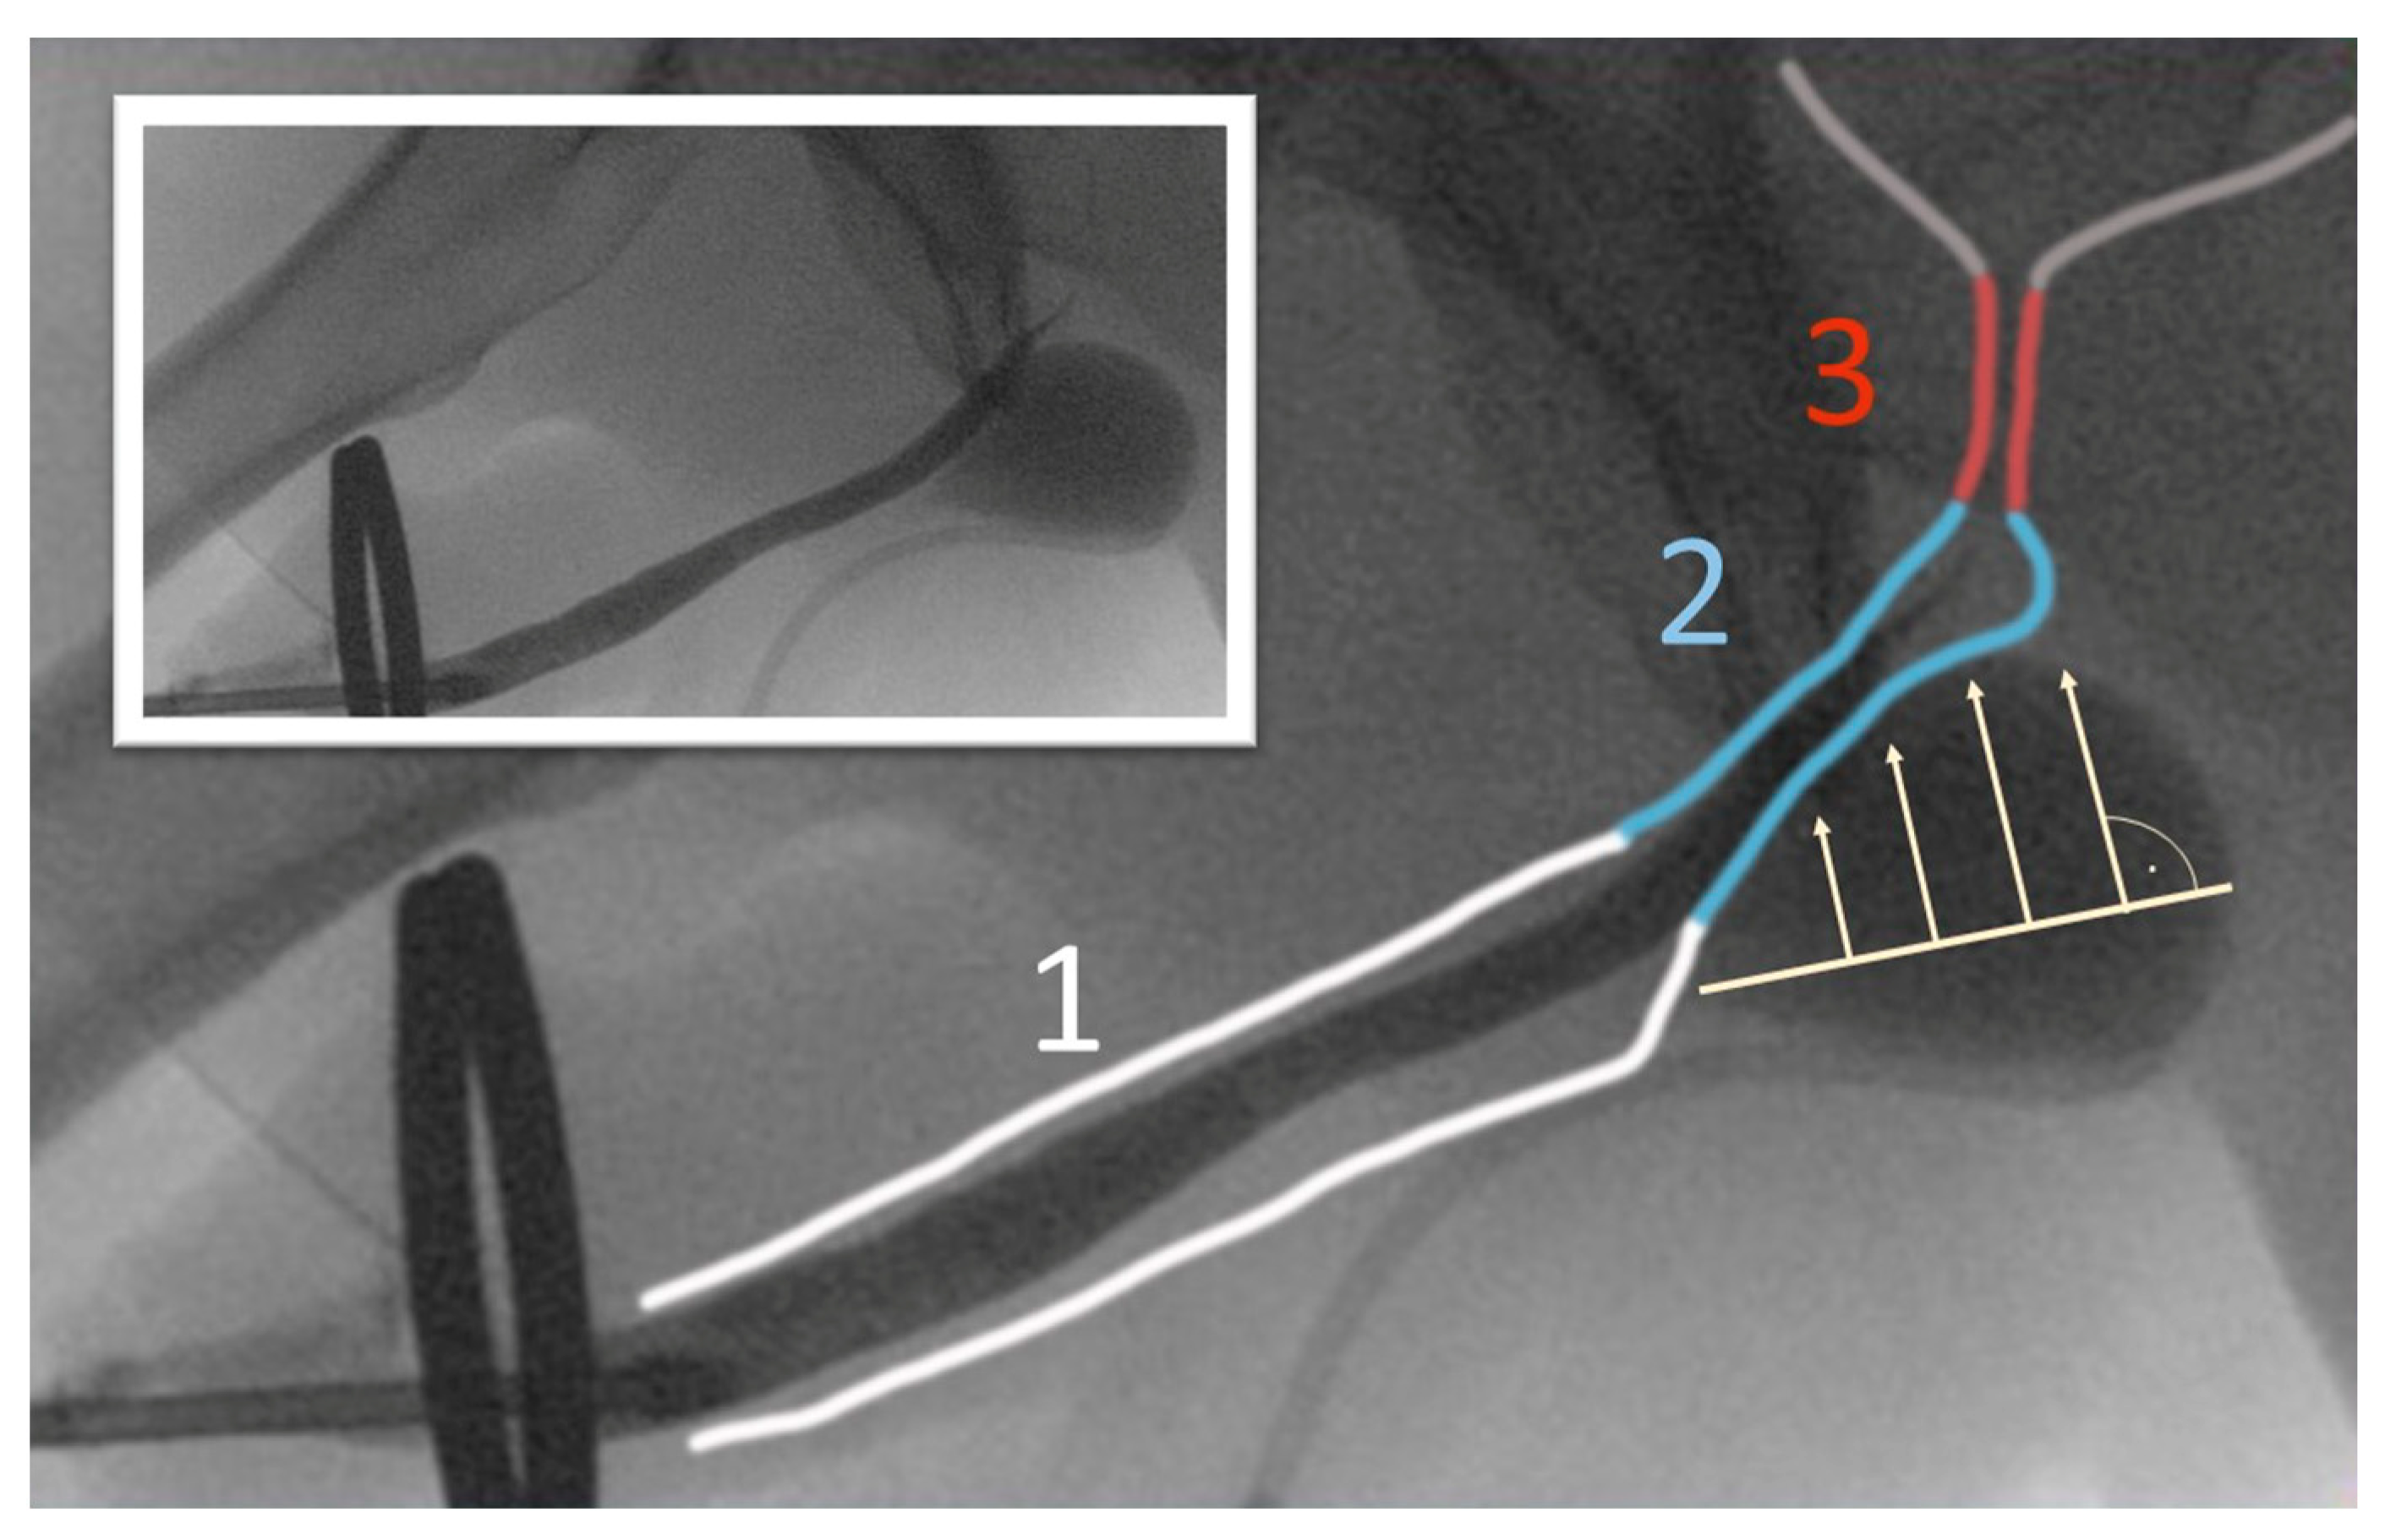

- Delivery of the tip of the tunneller paraurethrally below the hiatus urogenitalis, underneath the membranous urethra. As previously described by Rheder et al. for the fixed male Sling Advance, the entrance of the introducer needle tip into the perineal wound should be in the uppermost corner between the inferior pubic ramus and urethral bulb (Figure 5);